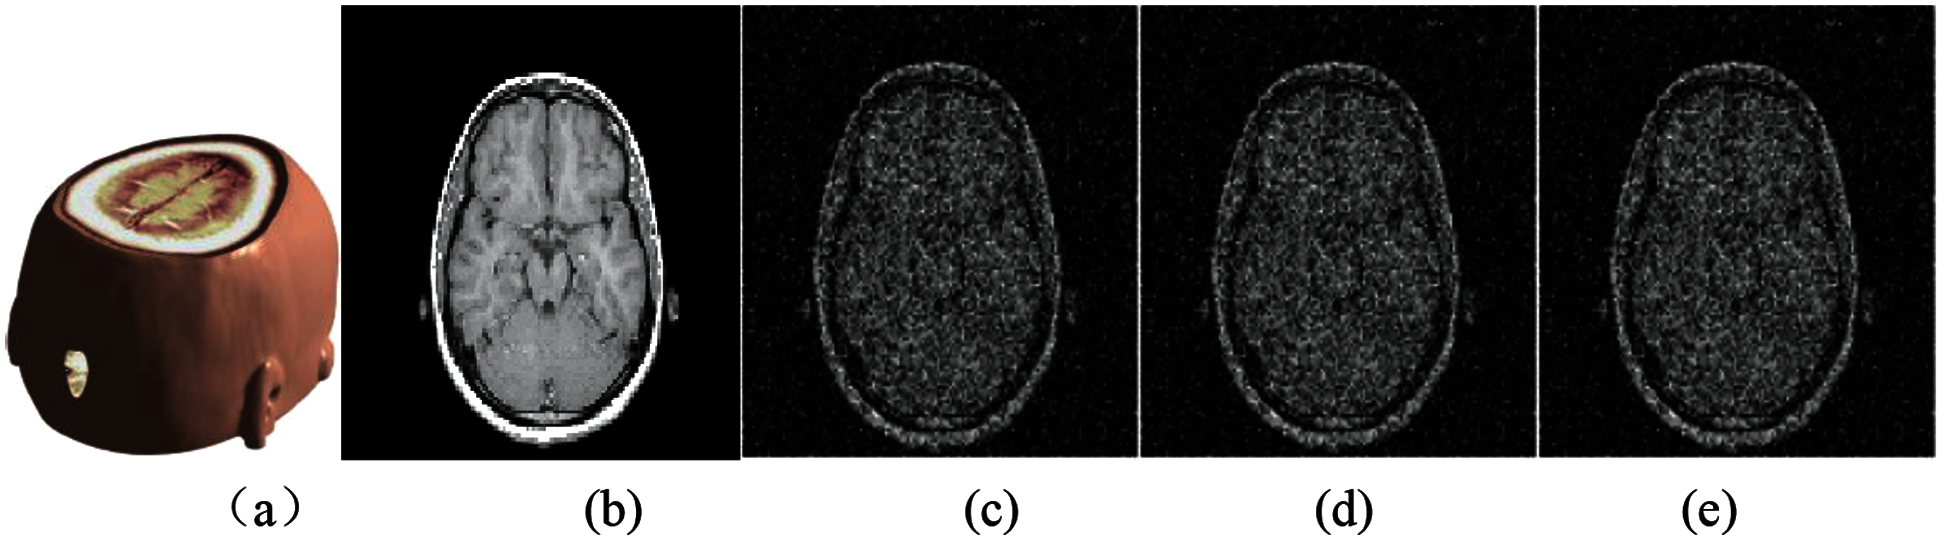

Gaussian noise attacks with different intensity are applied to medical data. Fig. 6 shows the medical model and brain slice image under the interference of three kinds of different Gaussian noise. It can be seen that the greater the intensity of Gaussian noise, the worse the quality of the slice image after being attacked. Tab. 1 shows the calculated PSNR and Normalized Correlation (NC) values under three kinds of Gaussian noise attacks with different intensities. It can be seen from the data that although the model is attacked, the quality of the extracted watermark image is still good, indicating that our algorithm has strong robustness to Gaussian noise.

Figure 6: The slice images of the watermarked brain data under Gaussian noise attacks with different intensities: (a) Watermarked brain volume data; (b) Slice of MRI brain data; (c) Slice attacked by Gaussian noise with 0.01variance; (d) Slice attacked by Gaussian noise with 0.15 variance; (e) Slice attacked by Gaussian noise with 0.40 variance